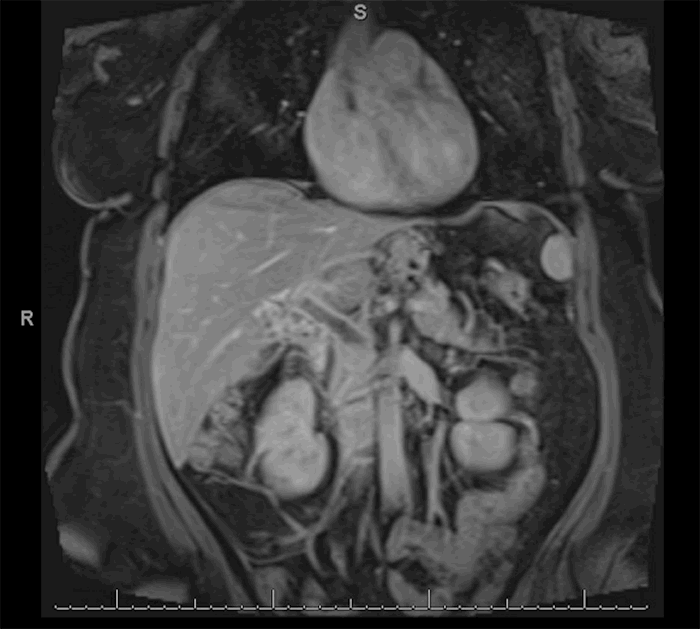

A 46-year-old morbidly obese African American woman presented with abdominal pain 13 days postlaparoscopic sleeve gastrectomy. Her pain was central and sharp in quality. She denied nausea, vomiting, or change in bowel habits. She also denied fever, chills, or dysuria. She was afebrile, hemodynamically stable, and her body mass index was 42.92. She had diffuse tenderness to deep palpation but did not exhibit peritoneal signs on exam. Labs were pertinent for mild leukocytosis, but electrolytes, blood urea nitrogen, and creatinine were within normal limits. Computed tomography (CT) of the abdomen and pelvis (Figure 1 and Figure 2) were suggestive of extensive portal vein thrombosis (PVT) that was confirmed with a follow-up ultrasound doppler study showing no flow in both branches as well as in the main portal vein (Figure 3 and Figure 4).

Figure 3. Echogenic intraluminal material in the right portal vein with no flow on color-flow doppler.

Figure 4. Color-flow doppler of main portal vein showing no flow.